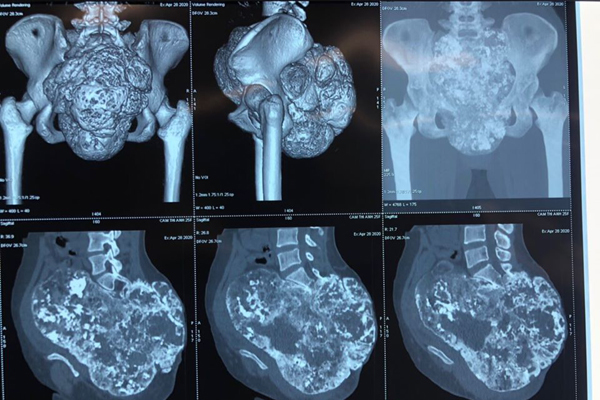

Hình ảnh khối u trên phim chụp

TS Phan Trọng Hậu, Chủ nhiệm khoa Chấn thương Chỉnh hình cột sống cho biết, khối u phát triển từ đầu xương cụt của Cầm Anh rất lớn, kích thước lên tới 21x21x15 cm, đè đẩy tử cung, buồng trứng, trực tràng, bàng quang ra trước, phát triển ra sau và xuống tầng sinh môn. Khối u đè ép vào niệu quản bên phải khiến thận phải teo nhỏ và chèn ép các mạch máu lớn, các dây thần kinh cùng cụt.